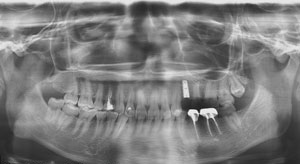

Chụp phim Panorama kiểm tra

![]() |

| Phim Panorama |

Dựa trên phim Panorama ta có thể thấy R24 bị tiêu xương ổ răng do mất răng lâu ngày

Kế hoạch điều trị: cấy 1 implant nâng đỡ R24, ghép xương

| Kiểm tra ghép xương và Implant R24 trên phim Panorama |